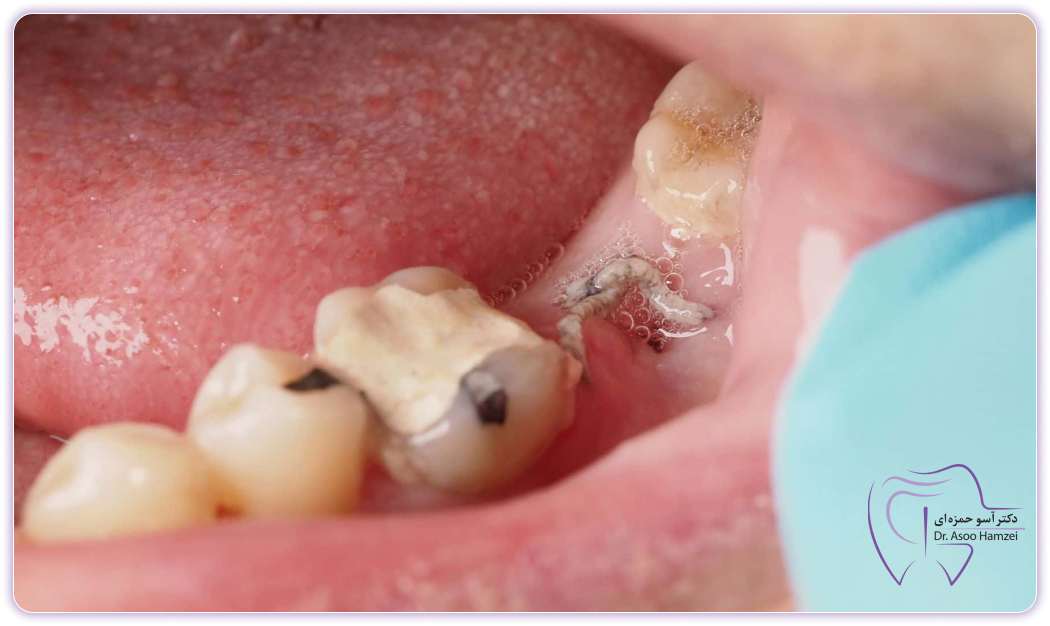

If your wisdom teeth are impacted or partially impacted, that is, they have not erupted from the gums or if half of them have erupted from the gums, they can create a source and a place for the accumulation of bacteria and food. In this case, these bacteria accumulate around the wisdom tooth and can eventually cause a wisdom tooth abscess or wisdom tooth abscess. If this infection is not treated, it can cause many problems and even transfer the infection into the blood and cause risks such as blood infection or even worse, so it is suggested to go to the dentist as soon as possible to treat the infection.

Wisdom tooth abscess in adults usually occurs when the soft tissues around the wisdom tooth, especially If the tooth is partially embedded or embedded, they will suffer from inflammation and accumulation of bacteria. This infection is known as perichronitis and causes pain, swelling, redness and may discharge pus and bad breath. Factors such as improper growth of wisdom teeth, accumulation of bacteria and lack of oral hygiene can lead to this type of infection, which may lead to more serious problems if left untreated.

After surgery or wisdom tooth extraction, there is a possibility of infection caused by the penetration of bacteria into the surgical site or the accumulation of food in the remaining cavity. Symptoms of infection after wisdom tooth extraction include severe and persistent pain, abnormal swelling, discharge of yellow or white pus, prolonged bleeding, fever, and difficulty opening the mouth.